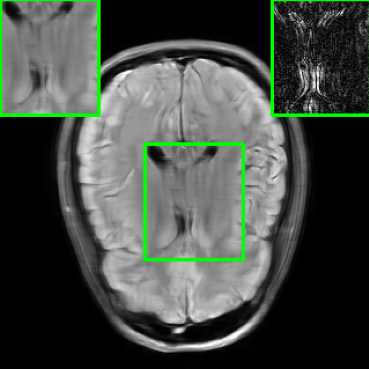

In addition to additive perturbations, the study presented in [32] underscores an additional potential source of instability that MoDL may face during testing. This source stems from changes in the measurement sampling rate, leading to perturbations in the sparsity of the sampling mask within [10]. Furthermore, in this paper, we consider another variation that MoDL could encounter during the testing phase, involving a shift in the k-space sampling locations within the matrix , resulting in the construction of a nonidentical forward operator for testing. For this case, , where . Figure 1 illustrates reconstructed images from the instabilities considered in this paper.

| PSNR = 29.8 dB | PSNR = 22.01 dB | PSNR = 20.28 dB | PSNR = 23.14 dB |

| (a) | (b) | (c) | (d) |

5.4 Visualizations

We now present visual samples from both the knee and brain datasets. Specifically, Figure 5 presents visual comparison of image reconstructions and their associated reconstruction errors within a closely examined region. Each image in the figure includes two inset panels in the top-left and top-right corners. The top-left inset panel, enclosed within a green bounding box, serves as a reference for the region of interest in the image. In contrast, the top-right inset panel depicts an error map in relation to the ground truth. Notably, our method stands out in its ability to capture the original image’s features, surpassing the performance of alternative methods (as also evident from the reported PSNR values). This visual comparison underscores the superior quality and accuracy of our approach in the robustification of the MRI image reconstruction task.